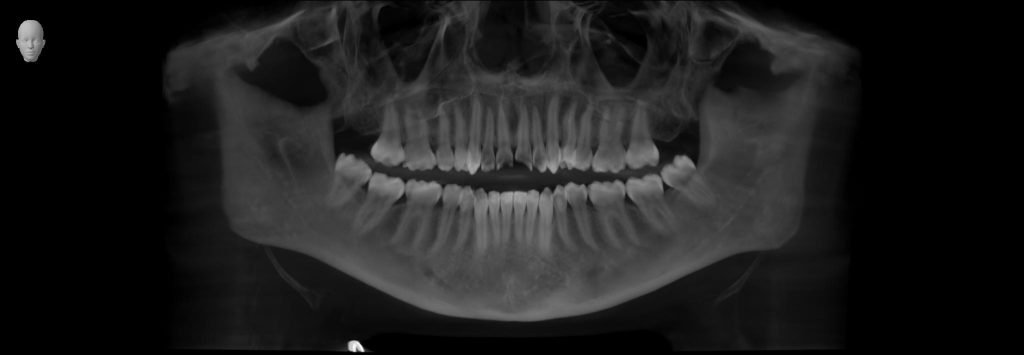

A detailed clinical and radiographic evaluation revealed the silent contributors behind his sleep struggles:

- Retrognathic mandible (recessed lower jaw) — restricting airway space

- Large, low-lying tongue — collapsing backward during sleep

- Airway analysis: Moderate to severe constriction

- Facial profile: Skeletal imbalance linked to airway narrowing

The diagnosis was clear:

His airway wasn’t just closing during sleep — it was structurally compromised.